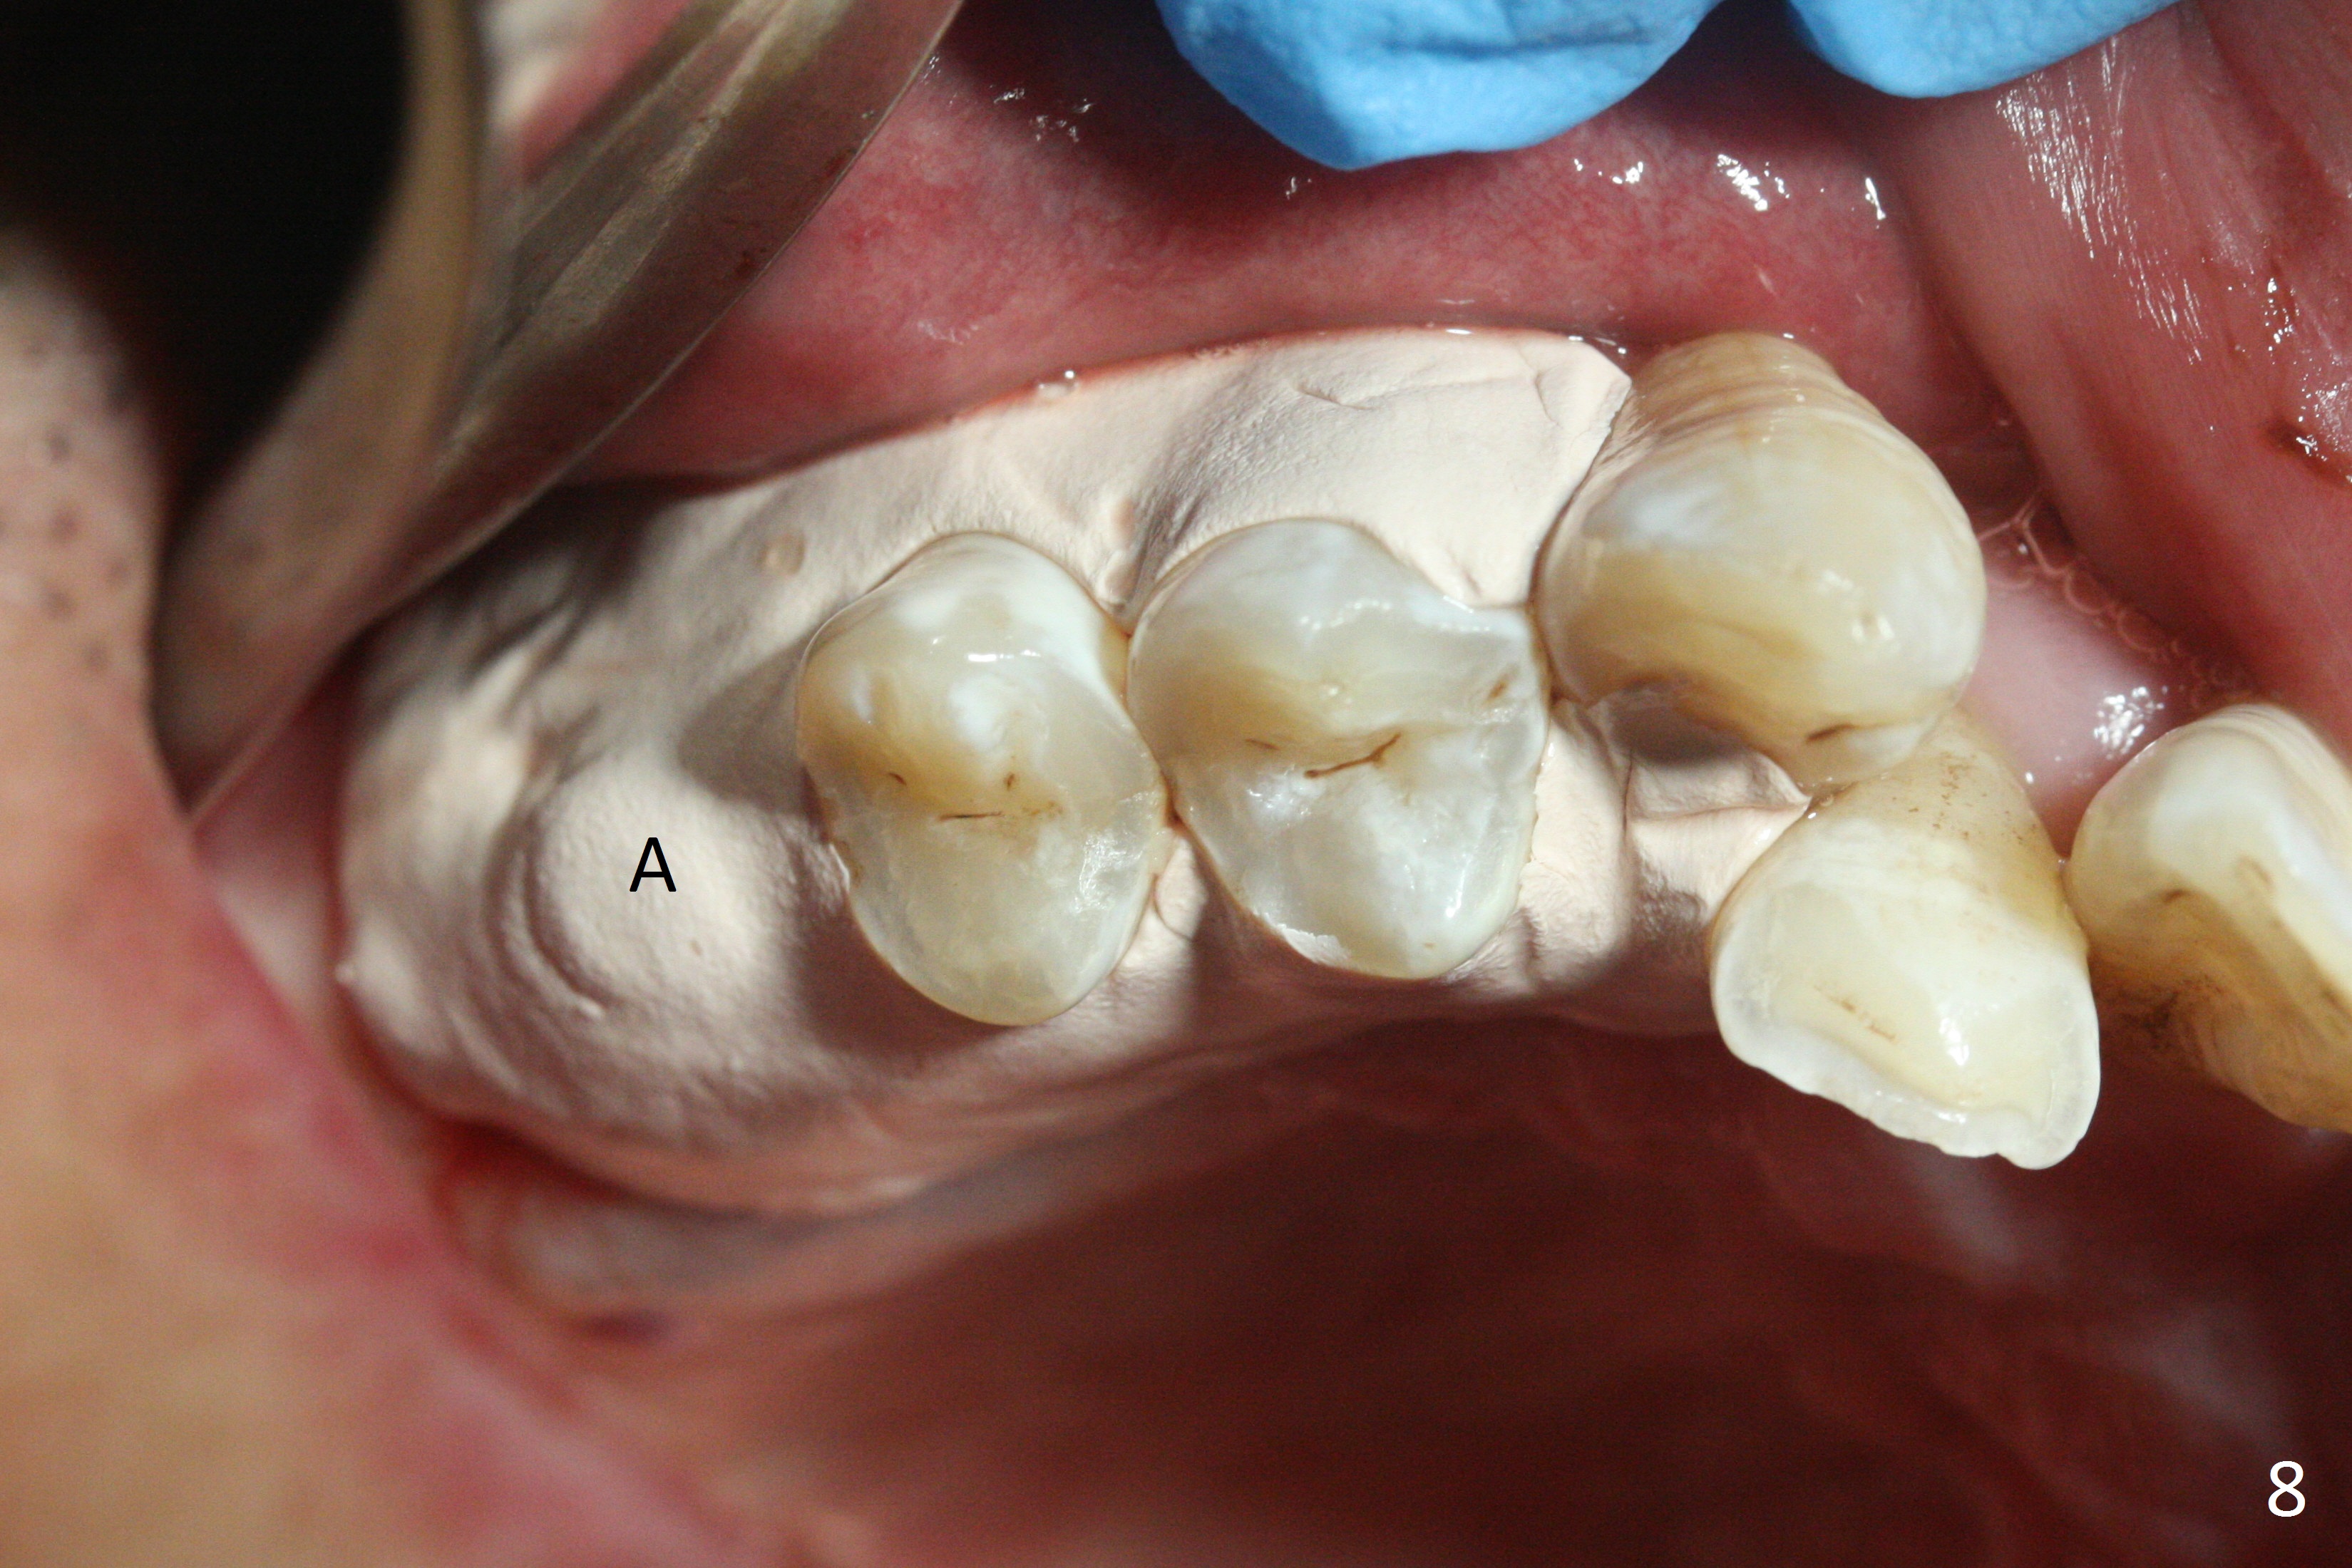

The palatal socket (Fig.1 P, packed with gauze) is intact, but implant trajectory may not be ideal. Buccal to the palatal socket are 2 pieces of the gingiva, buccal (B) and Septal (S). After the septal gingiva is pushed buccally (Fig.2 arrow), the underlying sloped septal bone is exposed (Fig.3 white area). Osteotomy is established as palatal as possible (Fig3 black circle) using DIO Sinus Master Kit, supplemented by Tatum osteotomes and DIO SM 3.8 mm tap drill for final sinus lift (Fig.4). Following further osteotomy using 4.1 and 4.5 mm taps, a 4.5x10 mm implant (Fig.6,7) with insertion torque >65 Ncm. Due to buccal bone loss, the coronal buccal threads are exposed 1-2 mm, which is covered by combination of allograft, autogenous bone and Osteogen. Prior to implantation, PRF plug and bone graft are used for sinus lift. The septal gingiva now is approximately 1-2 mm coronal to the implant plateau (Fig.5 S). The most coronal buccal gingival defect is covered by 3 pieces of PRF membrane (Fig.5 M) against a 6.8x5.5(6) mm abutment (A). Finally the socket is protected by periodontal dressing (Fig.8).